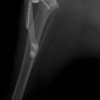

術前左後肢側面像

本症例は、走った後に左後肢を挙上していることを主訴に来院されました。触診時に左膝関節のクリック音を聴取、レントゲン検査にて左脛骨の前方変位が認められました。術中に、前十字靱帯の断裂及び内側半月板の損傷、内側の軟部組織の顕著な腫脹を確認。半月板切除、TPLOを実施しました。周囲組織への炎症の波及もあったため回復に時間を要しておりますが、徐々に跛行頻度は減少傾向にあり、現在も経過観察中です。術前に約29°あったTPAは術後に約10°まで矯正されました。